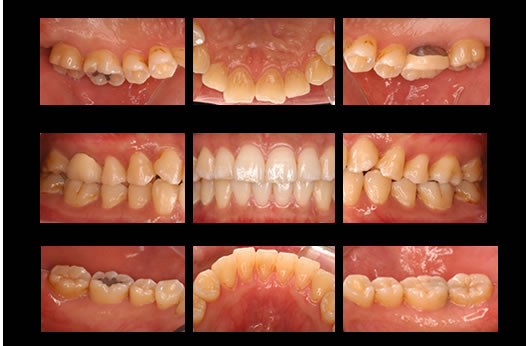

症例4

治療の特徴(患者I様)

初診時においては物を咬むと違和感が強く歯周外科処置を行いました。

骨のラインが部分的に増え、平坦にきれいに治っています。

2019年5月20日現在

口腔内写真

歯肉の状態、歯石の付き具合歯並び、咬み合わせ、歯の形態などをチェックします。

治療後の口腔内の変化の説明にも使用します。